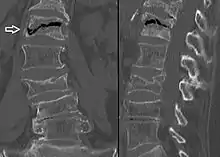

Example of vertebral compression fracture.

A potential complication of a vertebral compression fracture is avascular necrosis of the vertebral body, which is called Kümmel's disease, and may appear with the intravertebral vacuum cleft sign (at white arrow in image).[4]